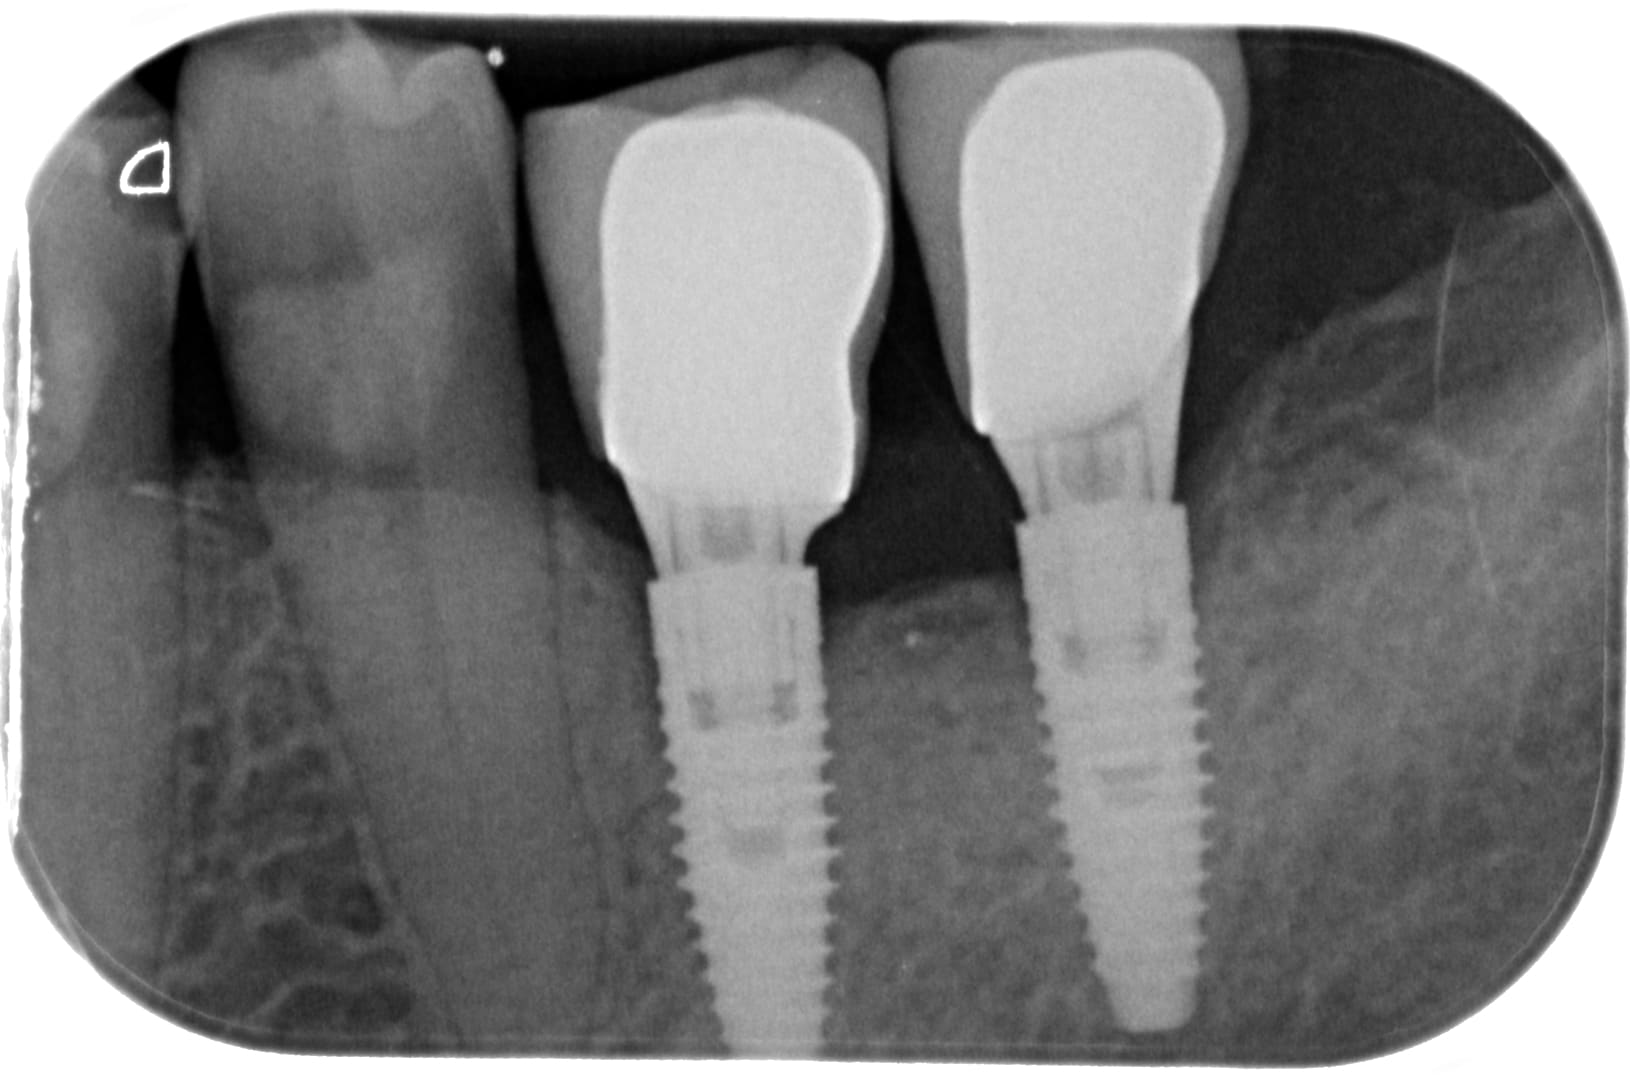

Pour la conjointe j ose pas tester... et j ai aucun pbm avec mes silicones donc j ose pas trop... et je fais beaucoup trop d ic ;))) et trop de sectorielles.

Mais serieusement, a mon avis une alginate bien traitée et preparation hurrimix, tu as du resultat en conjointe... mais attention aux déchirements.